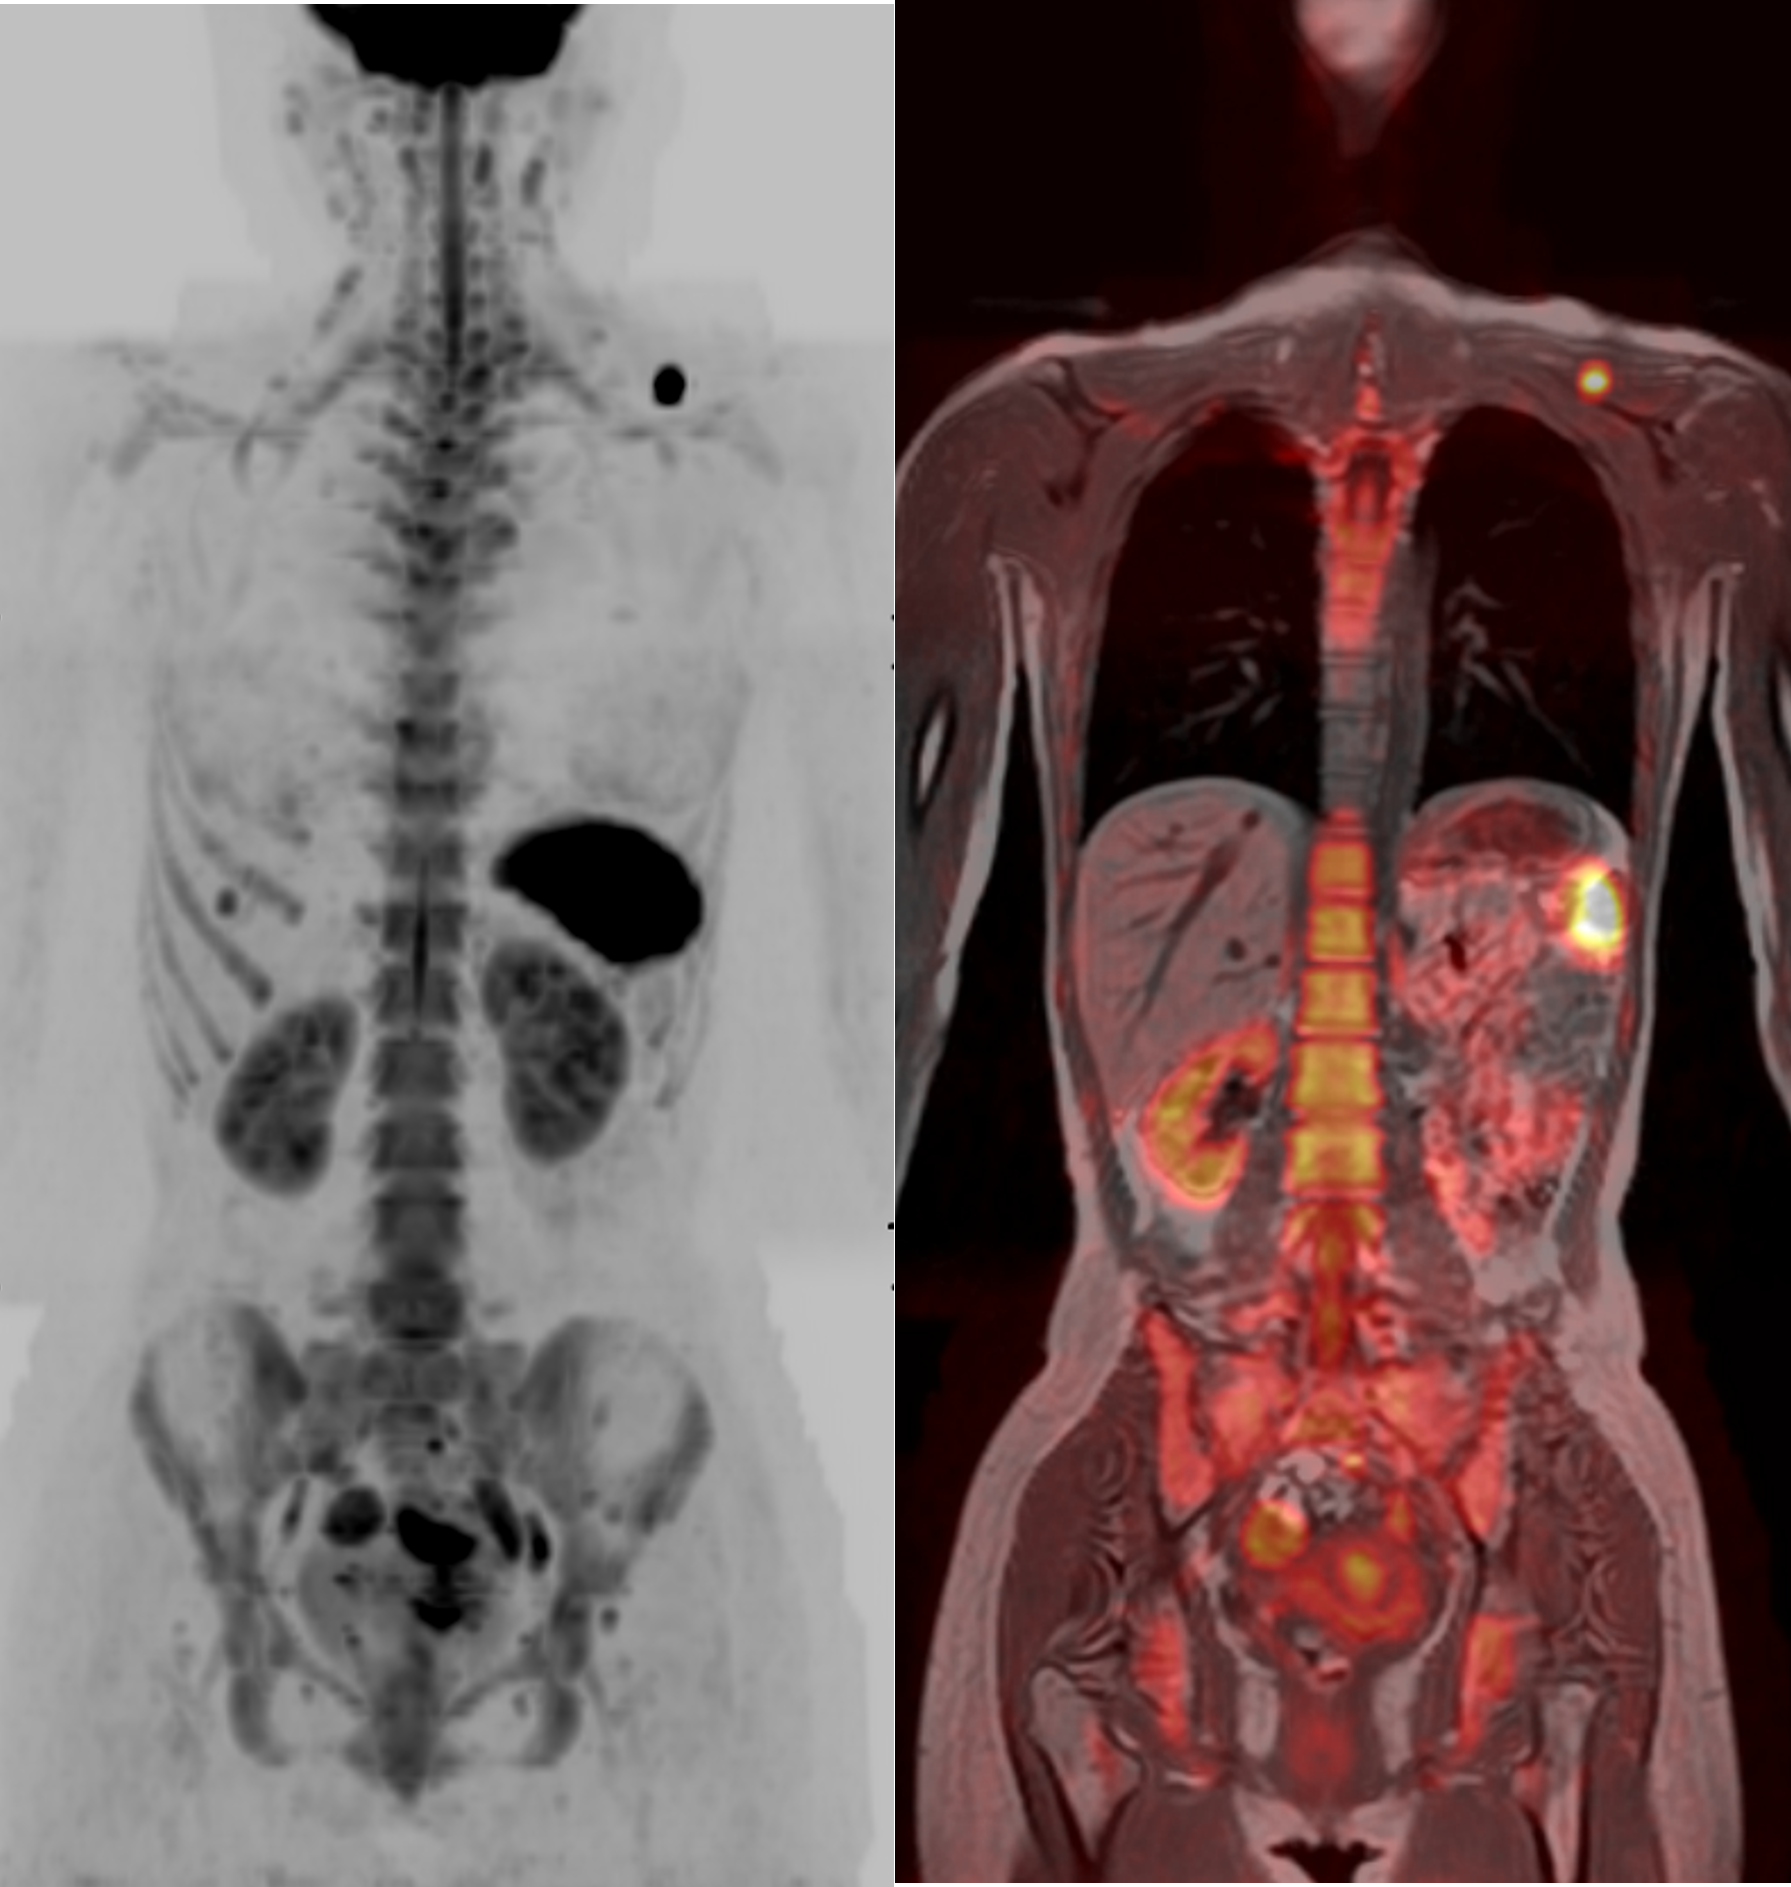

当院では、全身のがんを低侵襲で検出できる新しい画像検査技術「DWIBS(拡散強調全身MRI)」を開始しました。

DWIBSは、MRIを用いて全身を撮影することで、PET-CTのようにがんの早期発見を可能にする検査です。放射線被ばくがなく、造影剤も使用しないため、体への負担が少ないのが特長です。特に以下のような方におすすめです。